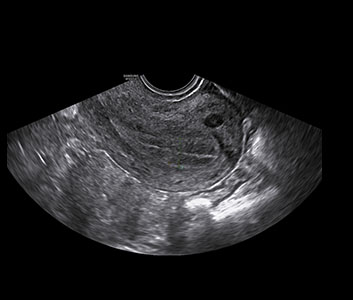

Follicule

Le monitorage d'ovulation permet de suivre l'évolution de la taille des follicules dans le cadre d'une stimulation ovarienne.